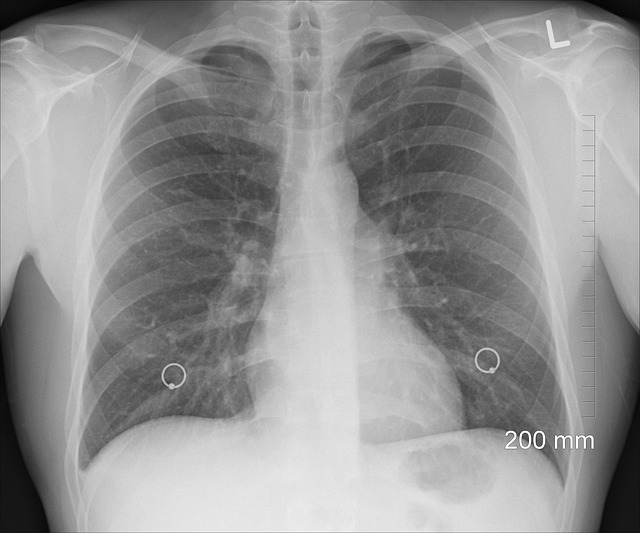

Come si prende una pleurite? La più comune causa è la polmonite, ma naturalmente non è la sola responsabile. Può essere causata da un virus (come l’influenza), da batteri o altre infezioni nei polmoni. La pleurite può essere acuta o cronica. La sua diagnosi avviene generalmente attraverso l’anamnesi, l’esame obiettivo e l’auscultazione del torace. Possono essere effettuati anche esami come la radiografia del torace, la tomografia computerizzata (TC) o la risonanza magnetica (RM) per determinare la causa dell’infiammazione della pleura. Il trattamento della pleurite dipende dalla causa sottostante.